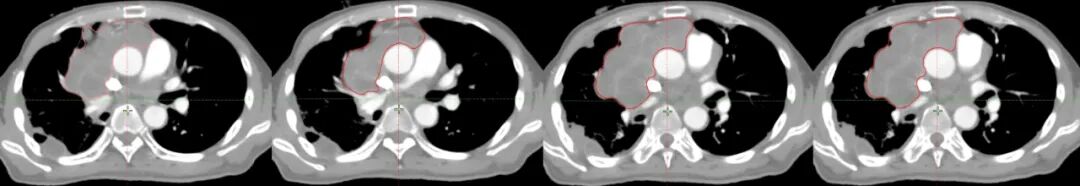

羅先生,55歲,自2010年診斷胸腔內(nèi)惡性孤立性纖維腫瘤,先后接受多次手術(shù)和化療,病情仍反復(fù)進展?;颊叻e極嘗試多種新型治療手段,包括粒子植入術(shù)、動脈灌注術(shù),并接受縱隔腫瘤切除和心包腫瘤切除手術(shù),以及多種化療藥物、靶向藥和免疫藥物治療,然而腫瘤仍持續(xù)進展?;颊呷胱』葜萑悍暖熆茣r,腫瘤病灶增殖快速,基本侵占整個縱膈,并向下侵犯,突破膈肌,侵入腹腔。面對如此巨大的病灶,且纖維肉瘤對放化療敏感性不佳,常規(guī)照射技術(shù)無法控制。放療科團隊決定采用空間分割放療技術(shù)進行治療。

圖注:放射治療靶區(qū)及劑量分布圖。紅線是放射治療靶區(qū);綠色球體為放射治療高劑量分布,可見聚焦照射,周邊劑量快速跌落,周圍組織受到良好保護。